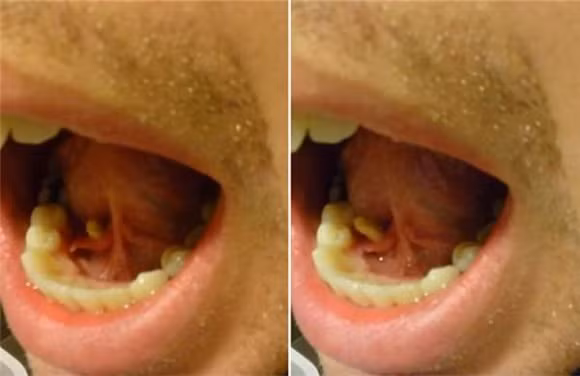

Thay vì theo dõi theo yêu cầu của bác sĩ, quá khó chịu với sự xuất hiện của viên sỏi, về nhà Brandon Douglas đã tự đưa viên sỏi ra ngoài bằng cách uốn lưỡi, và sau vài lần đẩy lưỡi một vật thể dần dần chui ra khỏi tuyến nước bọt. Anh chàng khi đó vừa ăn sáng xong đã quyết định chộp lấy điện thoại rồi vào nhà tắm quay lại cảnh tượng đang diễn ra trong miệng mình.

Sau khi nó đã chui ra, Brandon Douglas dùng tay kéo nó ra ngoài và hoảng sợ khi thấy “viên sỏi” dài gần 4 cm. Anh cho biết trong quá trình ép viên sỏi ra không hề thấy đau đớn.